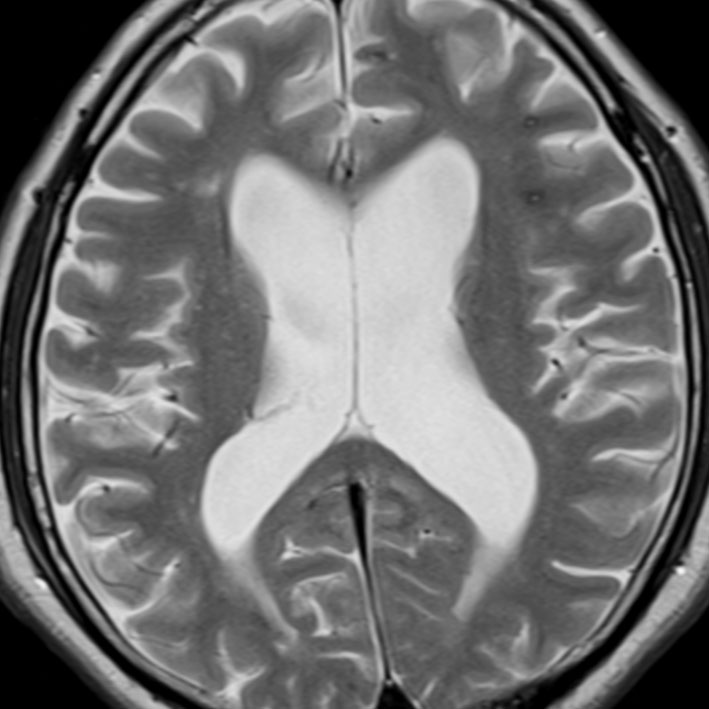

水頭症

水頭症です,側脳室体部がぷーっと膨らんで,中に髄液が大量にたまっています。

これは64歳男性の中脳水道閉塞症による閉塞性水頭症で,これでも無症状でした。